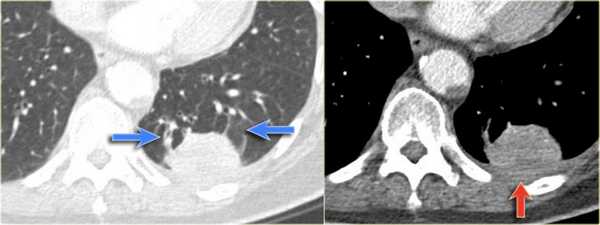

Локальный плеврит является причиной утолщения плевры. Далее происходит инвагинация субплевральной легочной паренхимы с характерным дугообразным искривлением сосудов, и ателектаз принимает округлую форму. Симптом хвоста кометы — это симптом, который визуализируется в виде кометообразного хвоста из сосудов и воздухоносных путей, направленных к корню легкого.

На боковой рентгенограмме выявляется образование, которое исходит из плевры. На первый взгляд — это образование, исходящее из плевры.

Далее перейдите к оценки КТ-снимков.

На КТ четко выявлено, что это образование легкого. Для многих данные изменения на КТ заставили бы задуматься о раке легкого. Красной стрелкой указана утолщение плевры, а синими стрелками указаны сосуды вокруг данного образования, что называют хвостом кометы.

Всякий раз, когда встречается образование, сочлененное с плеврой, а также похожее на рак легкого, то не забудьте об округлом ателектазе.

Округлый ателектаз — это доброкачественные изменения, которые на последующих снимках не изменяются в размерах и чаще встречаются у пациентов, которые имели контакт с асбестом.

В левой нижней доле визуализируются изменения высокой плотности. На фронтальной рентгенограмме данное образование выглядит схоже с консолидацией так, как на боковой границы острые, то скорее это образование. Красной стрелкой указано утолщение плевры.

Несмотря на то, что легочный рак находится на вершине нашего дифференциального ряда, данные изменения характерны для округлого ателектаза, что хорошо визуализируется на КТ (утолщение плевры, овальная форма, симптом хвоста кометы).